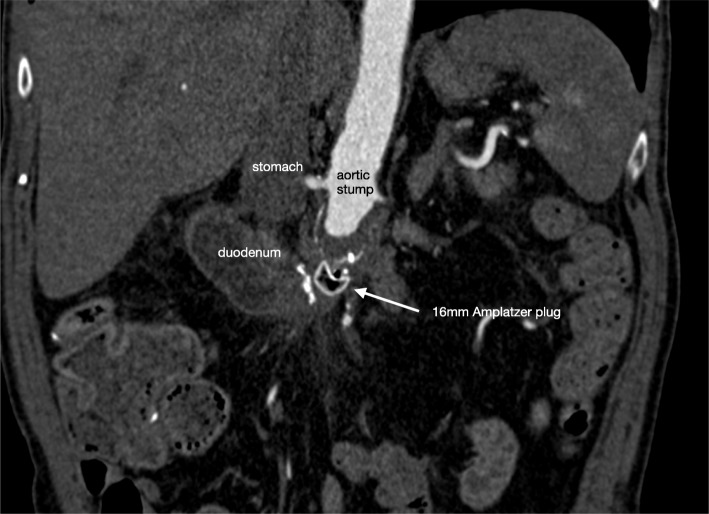

Fig. 3.

CTA abdomen with the Amplatzer® plug in situ after 3 months. CTA after 3 months showed thrombosis of the aortic stump with the Amplatzer® Vascular Plug in situ